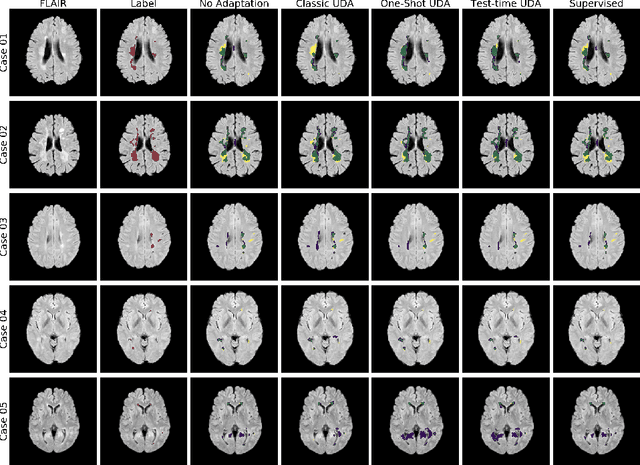

Abstract:Convolutional neural networks trained on publicly available medical imaging datasets (source domain) rarely generalise to different scanners or acquisition protocols (target domain). This motivates the active field of domain adaptation. While some approaches to the problem require labeled data from the target domain, others adopt an unsupervised approach to domain adaptation (UDA). Evaluating UDA methods consists of measuring the model's ability to generalise to unseen data in the target domain. In this work, we argue that this is not as useful as adapting to the test set directly. We therefore propose an evaluation framework where we perform test-time UDA on each subject separately. We show that models adapted to a specific target subject from the target domain outperform a domain adaptation method which has seen more data of the target domain but not this specific target subject. This result supports the thesis that unsupervised domain adaptation should be used at test-time, even if only using a single target-domain subject